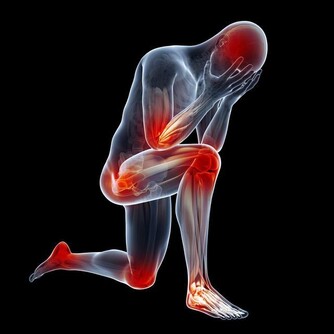

8.關節僵硬

晨僵的原因是由於在睡眠或活動減少時,使受累關節周圍組織滲液或充血水腫,

引起關節周圍肌肉組織緊張,而使關節腫痛或僵硬不適。

隨著肌肉的收縮,水腫液被淋巴管和小靜脈所吸收,晨僵隨之緩解。

可能導致晨僵的疾病包括:強直性脊柱炎、類風濕性關節炎、腰肌勞損、風濕性多肌痛、軟組織損傷、椎管狹窄等。

此外,一些過敏性病症,如多形性紅斑、皮肌炎、紅斑狼瘡、硬皮病等,也會出現明顯的晨僵現象。

因此在出現晨僵症狀後應及時到醫院就診,查明病因並及時治療。